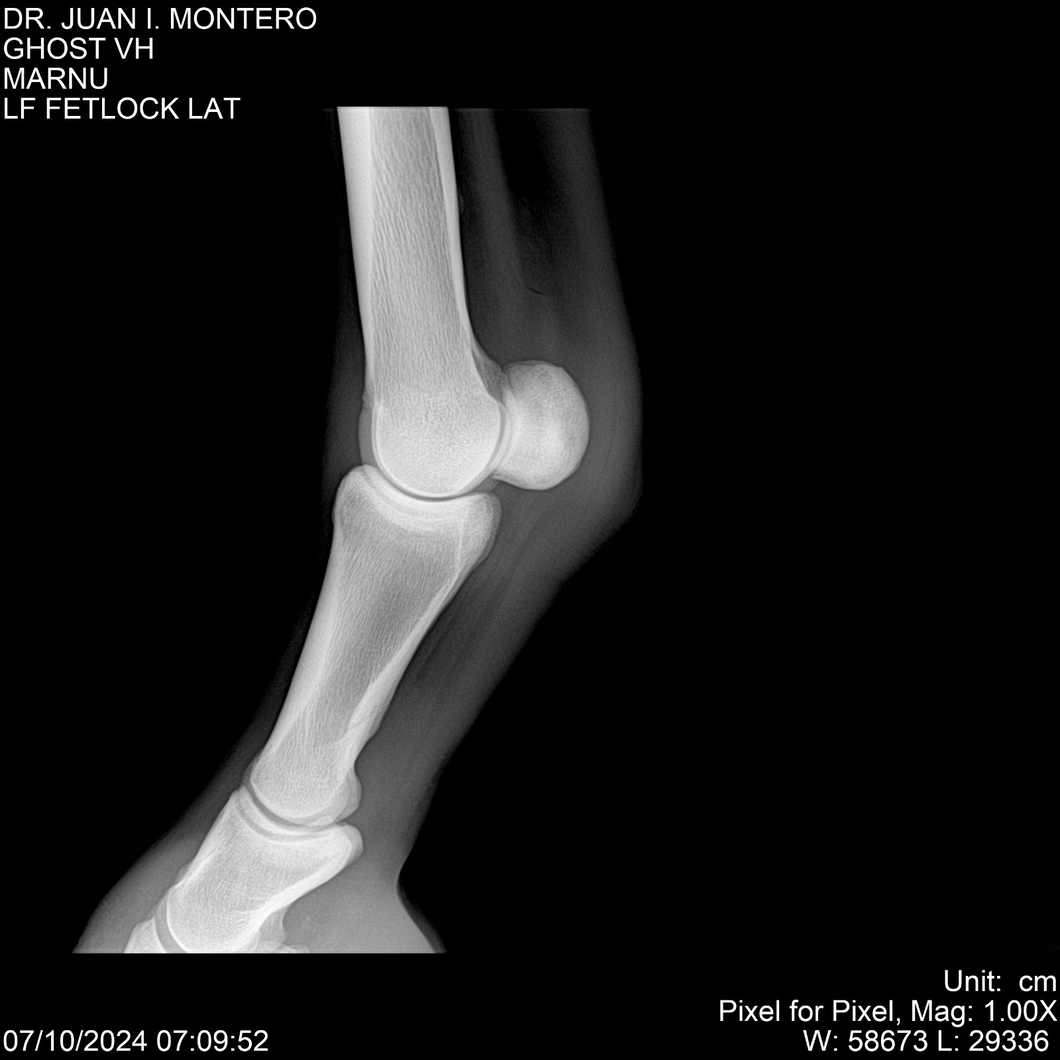

LOTE 15, GHOST VH 🔥 🔥 🔥 Lote Anterior Volver al remate Lote Siguiente Ficha Contacto Montevideo - Ficha del Lote Identificador: #282525 Categoría: Yeguarizos Montevideo - 69 Visualizaciones ClicData Contacto Empresa: Abelenda N. R., Walter Hugo Nombre*: Teléfono* : E-mail* : Mensaje Enviar Registrese gratis Este contenido Exclusivo está disponible sólo para usuarios registrados Ingresar